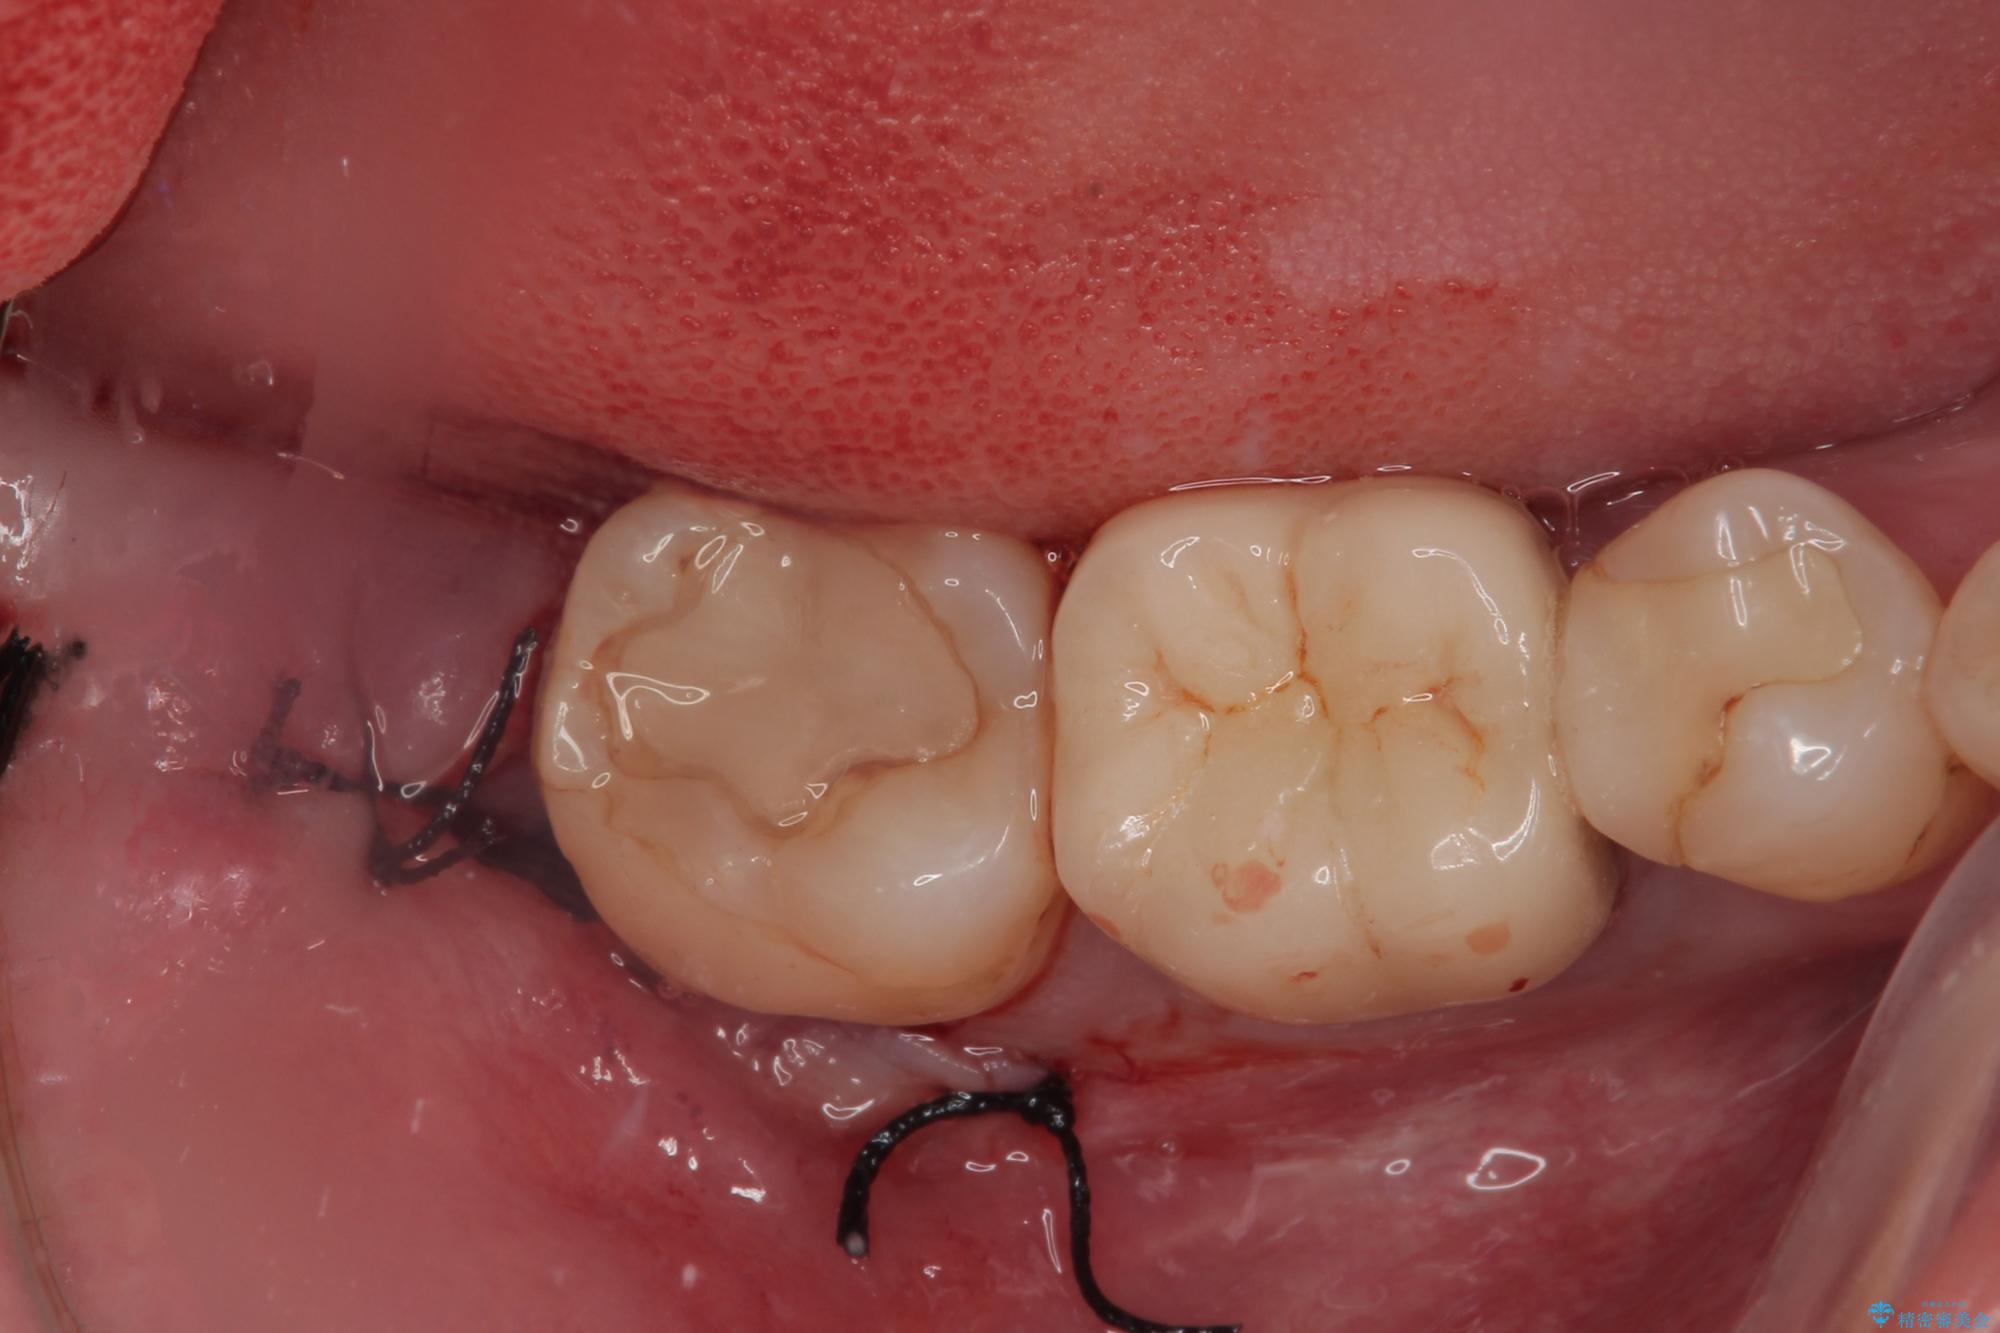

CTで神経の位置などを確認し、抜歯術を行いました。

一週間後に抜糸を行いました。

しっかり麻酔が効いたことを確認してから安全に抜歯を行いました。